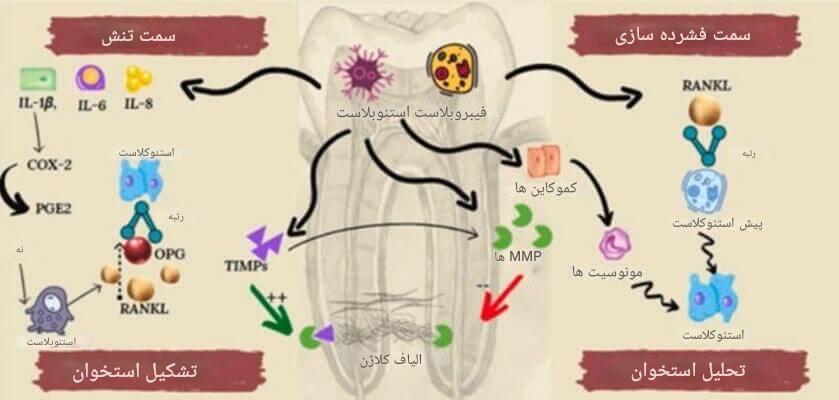

پس از آمادهسازی محیط توسط لیگامان پریودنتال، یکی دیگر از پاسخهای بیولوژیکی بدن به ارتودنسی مربوط به استخوان فک است تا پاسخ سازگاری خود را آغاز کند. استخوان آلوئول (بخشی از فک که دندانها را نگه میدارد) ساختاری زنده و پویاست که در پاسخ به تحریک مکانیکی، ساختار خود را بازسازی میکند. این مرحله حیاتی، حدود ۳ تا ۵ روز پس از اعمال نیروی ارتودنسی آغاز میشود.

در ناحیهی فشاری، سلولهایی به نام استئوکلاستها فعال میشوند. این سلولها با تجزیهی استخوان موجود، فضا را برای حرکت دندان باز میکنند—فرآیندی که به آن تحلیل استخوانی (bone resorption) گفته میشود. در سوی دیگر، یعنی ناحیه کشش، استئوبلاستها به صحنه میآیند تا با ساخت ماتریس استخوانی جدید، استخوان تازه بسازند— فرآیندی موسوم به استخوانسازی (bone formation).

نکتهی جالب این است که این تغییر بیولوژی حرکت دندان در ارتودنسی کاملاً هماهنگ و کنترلشده انجام میشود. بنابراین، استخوان اطراف دندان نهتنها تخریب نمیشود، بلکه متناسب با موقعیت جدید دندان، دوباره بازسازی میگردد. این بازسازی پیوسته باعث میشود که حرکت دندان پایدار، تدریجی و بدون آسیب به ساختارهای حمایتکننده انجام شود.

رشد سلولهای استخوانی و بازسازی بافت

در ادامهی تحلیل و ساخت مجدد استخوان، یکی دیگر از اتفاقات بیولوژیکی طی درمان ارتودنسی فعالیت گستردهتر سلولهای مسئول بازسازی بافت استخوانی است. این مرحله معمولاً از روز پنجم تا هفته دوم پس از اعمال نیروی ارتودنسی شروع میشود و بسته به شدت و جهت نیرو، چندین هفته ادامه دارد.

در این فاز، استئوکلاستها (سلولهای تجزیهکننده استخوان) در ناحیهی فشار بهطور فعال به تجزیهی بافت استخوانی ادامه میدهند. همزمان، استئوبلاستها (سلولهای سازنده استخوان) در سمت کشش، ماتریسی پروتئینی به نام استئوئید (osteoid) ترشح میکنند که پایهی اولیه استخوان جدید است. این ماتریس به مرور معدنی شده و به استخوان سخت تبدیل میشود.

در این بین، سلولهای دیگری نیز نقش دارند؛ مانند سلولهای بنیادی مزانشیمی که از مغز استخوان فراخوانده میشوند تا به استئوبلاست یا دیگر سلولهای مورد نیاز تمایز یابند. این تعاملات پیچیده با هماهنگی بیوشیمیایی و مکانیکی انجام میگیرد تا اطمینان حاصل شود که ساختار استخوان جدید هم از نظر عملکردی و هم از نظر پایداری با شرایط جدید دندانها سازگار است.